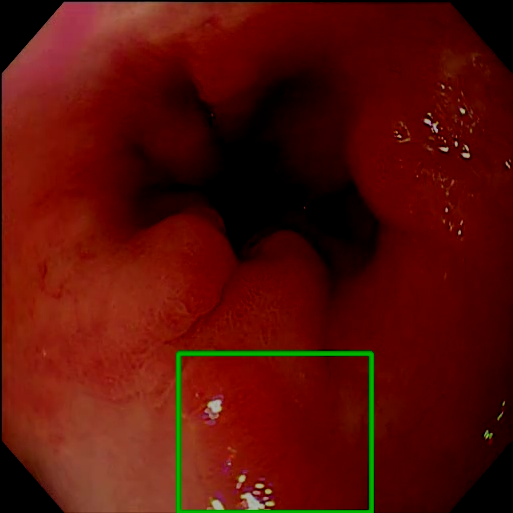

Gaussian Blur

Endoscopy GMAIMMbench Disease Diagnosis

Gaussian Blur - L0 (Original)

L0

L0 (Original)

Gaussian Blur - L1 (Moderate)

L1

L1 (Moderate)

Gaussian Blur - L2 (Severe)

L2

L2 (Severe)

Question

Focus on the square-highlighted area of this endoscopy image. What could be the potential diagnosis?

A barrett's esophagus B high-grade dysplasia C polyp D gastrointestinal tract cancer

Ground Truth: D. gastrointestinal tract cancer